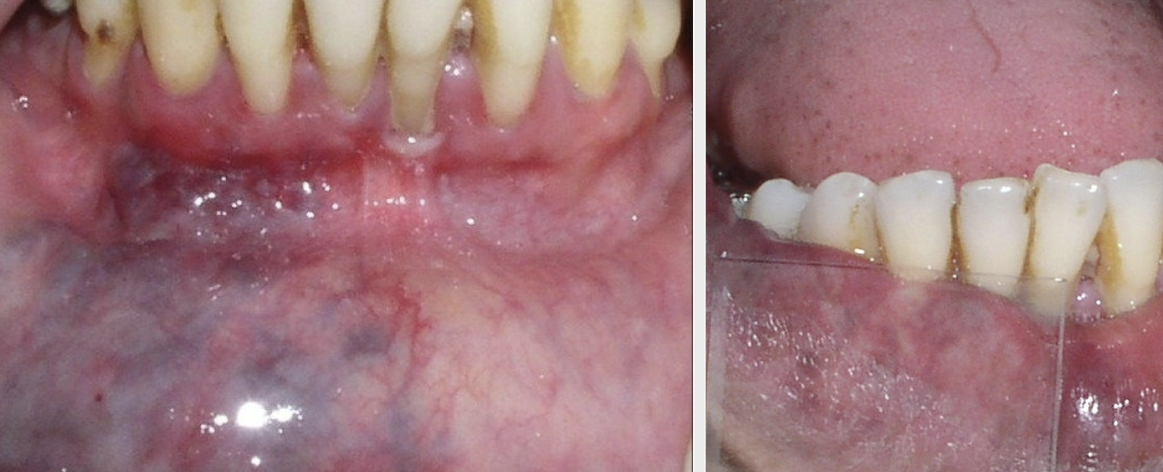

variation of normal; up to 90% of Black adults and 50% children (does not rub off)

leukoedema

leukoedema appearance

diffuse, gray-white, milky, opalescent

leukoedema most common locations

bilaterally on buccal mucosa

Does leukoedema require tx?

no